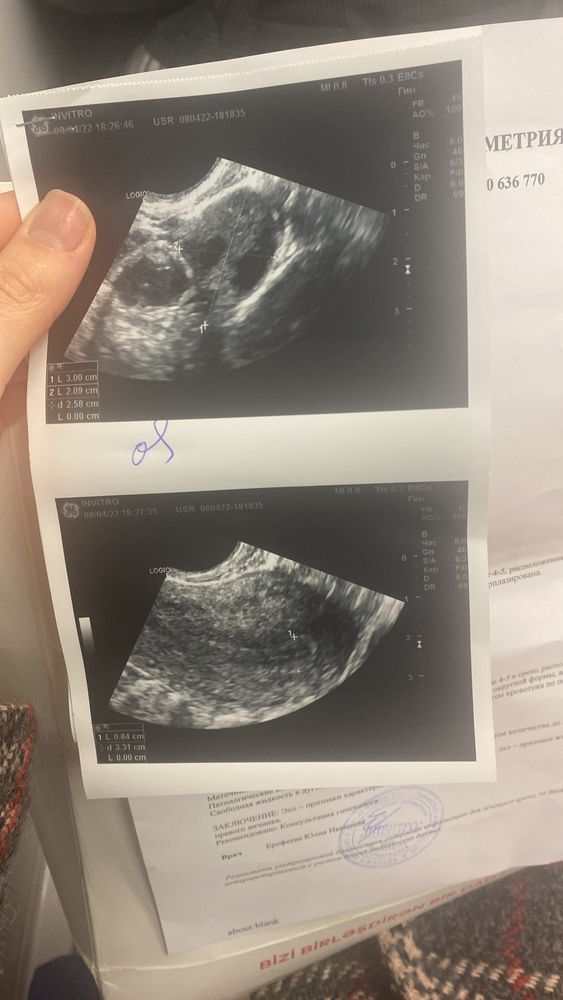

Люди и с 0.5 тут беременеют вы чего, это вполне отличный эндометрий. У меня в ЭКО протоколе был такой же эндометрий, врач сказал "переносим!"

Гузаль Нифталиева, мне вот тоже сегодня врач сказал ,что если при эко такие показатели ,то сразу переносят ,не все берутся( ну у меня овуляция была вчера. Если все таки яйцо оплодотворилось оно же до эндометрии идёт 5-7 дней,может все таки прикрепится ((

Эндометрий 16,6 нормально ли это девочки ?!?! Девочки скажите пожалуйста у кого была похожая ситуация ? У кого получалось забеременеть или только